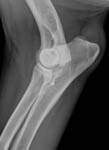

Gesundheitsstatus vom 26.11.2018 Die Röntgenbilder zeigen keinen Hinweis auf HD oder ED bei Lena vom Gehrensee. Die veterinärmedizinischen Untersuchungen von Jana auf HD, ED u. DCM und die Zuchtzulassungsprüfung wurden erfolgreich bestanden.

Die Gelenke sind HD und ED - frei, das Herz ohne Befund. Vor dem Hintergrund, dass seit 5 Generationen alle Zuchthündinnen bis ins hohe